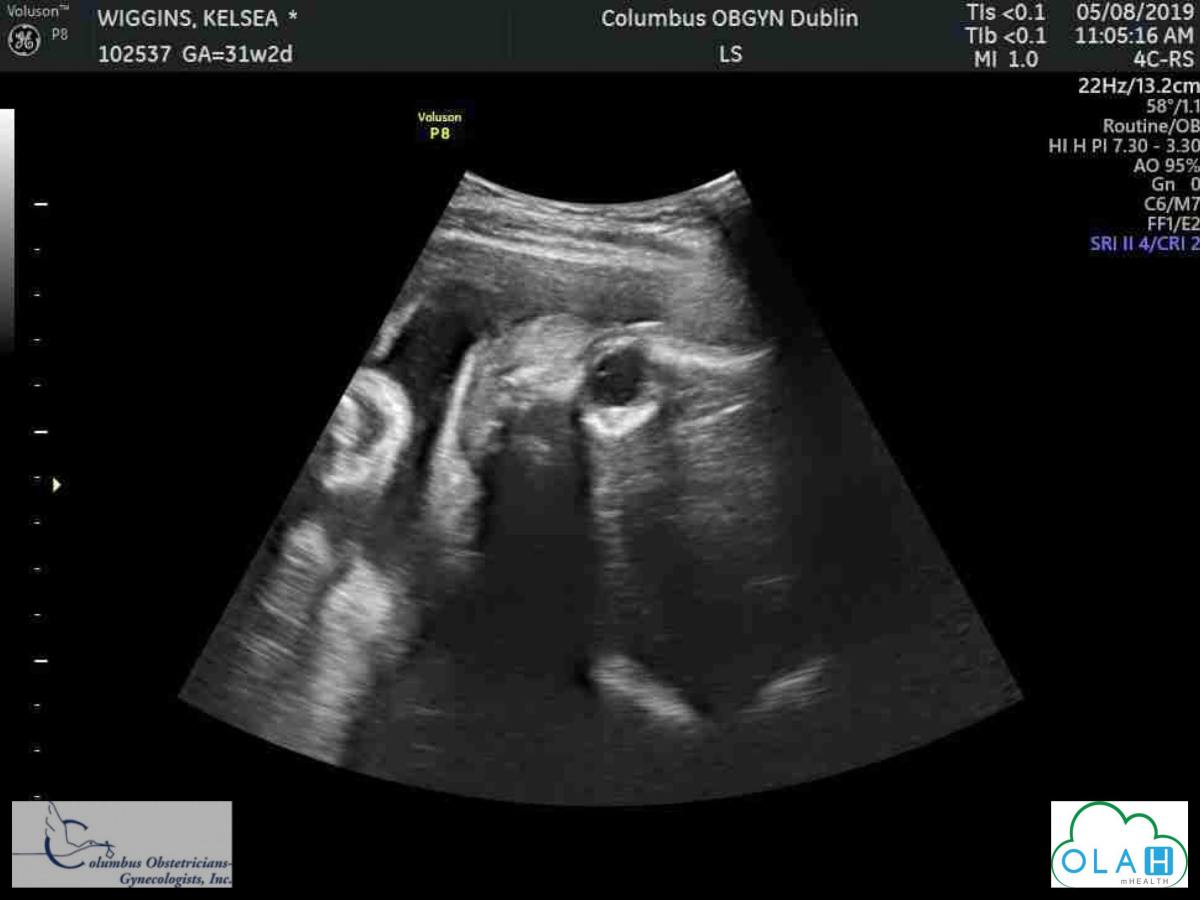

Dear Gunner…

An open letter to my joy and song: my unborn son, Gunner Xavier Cozad.